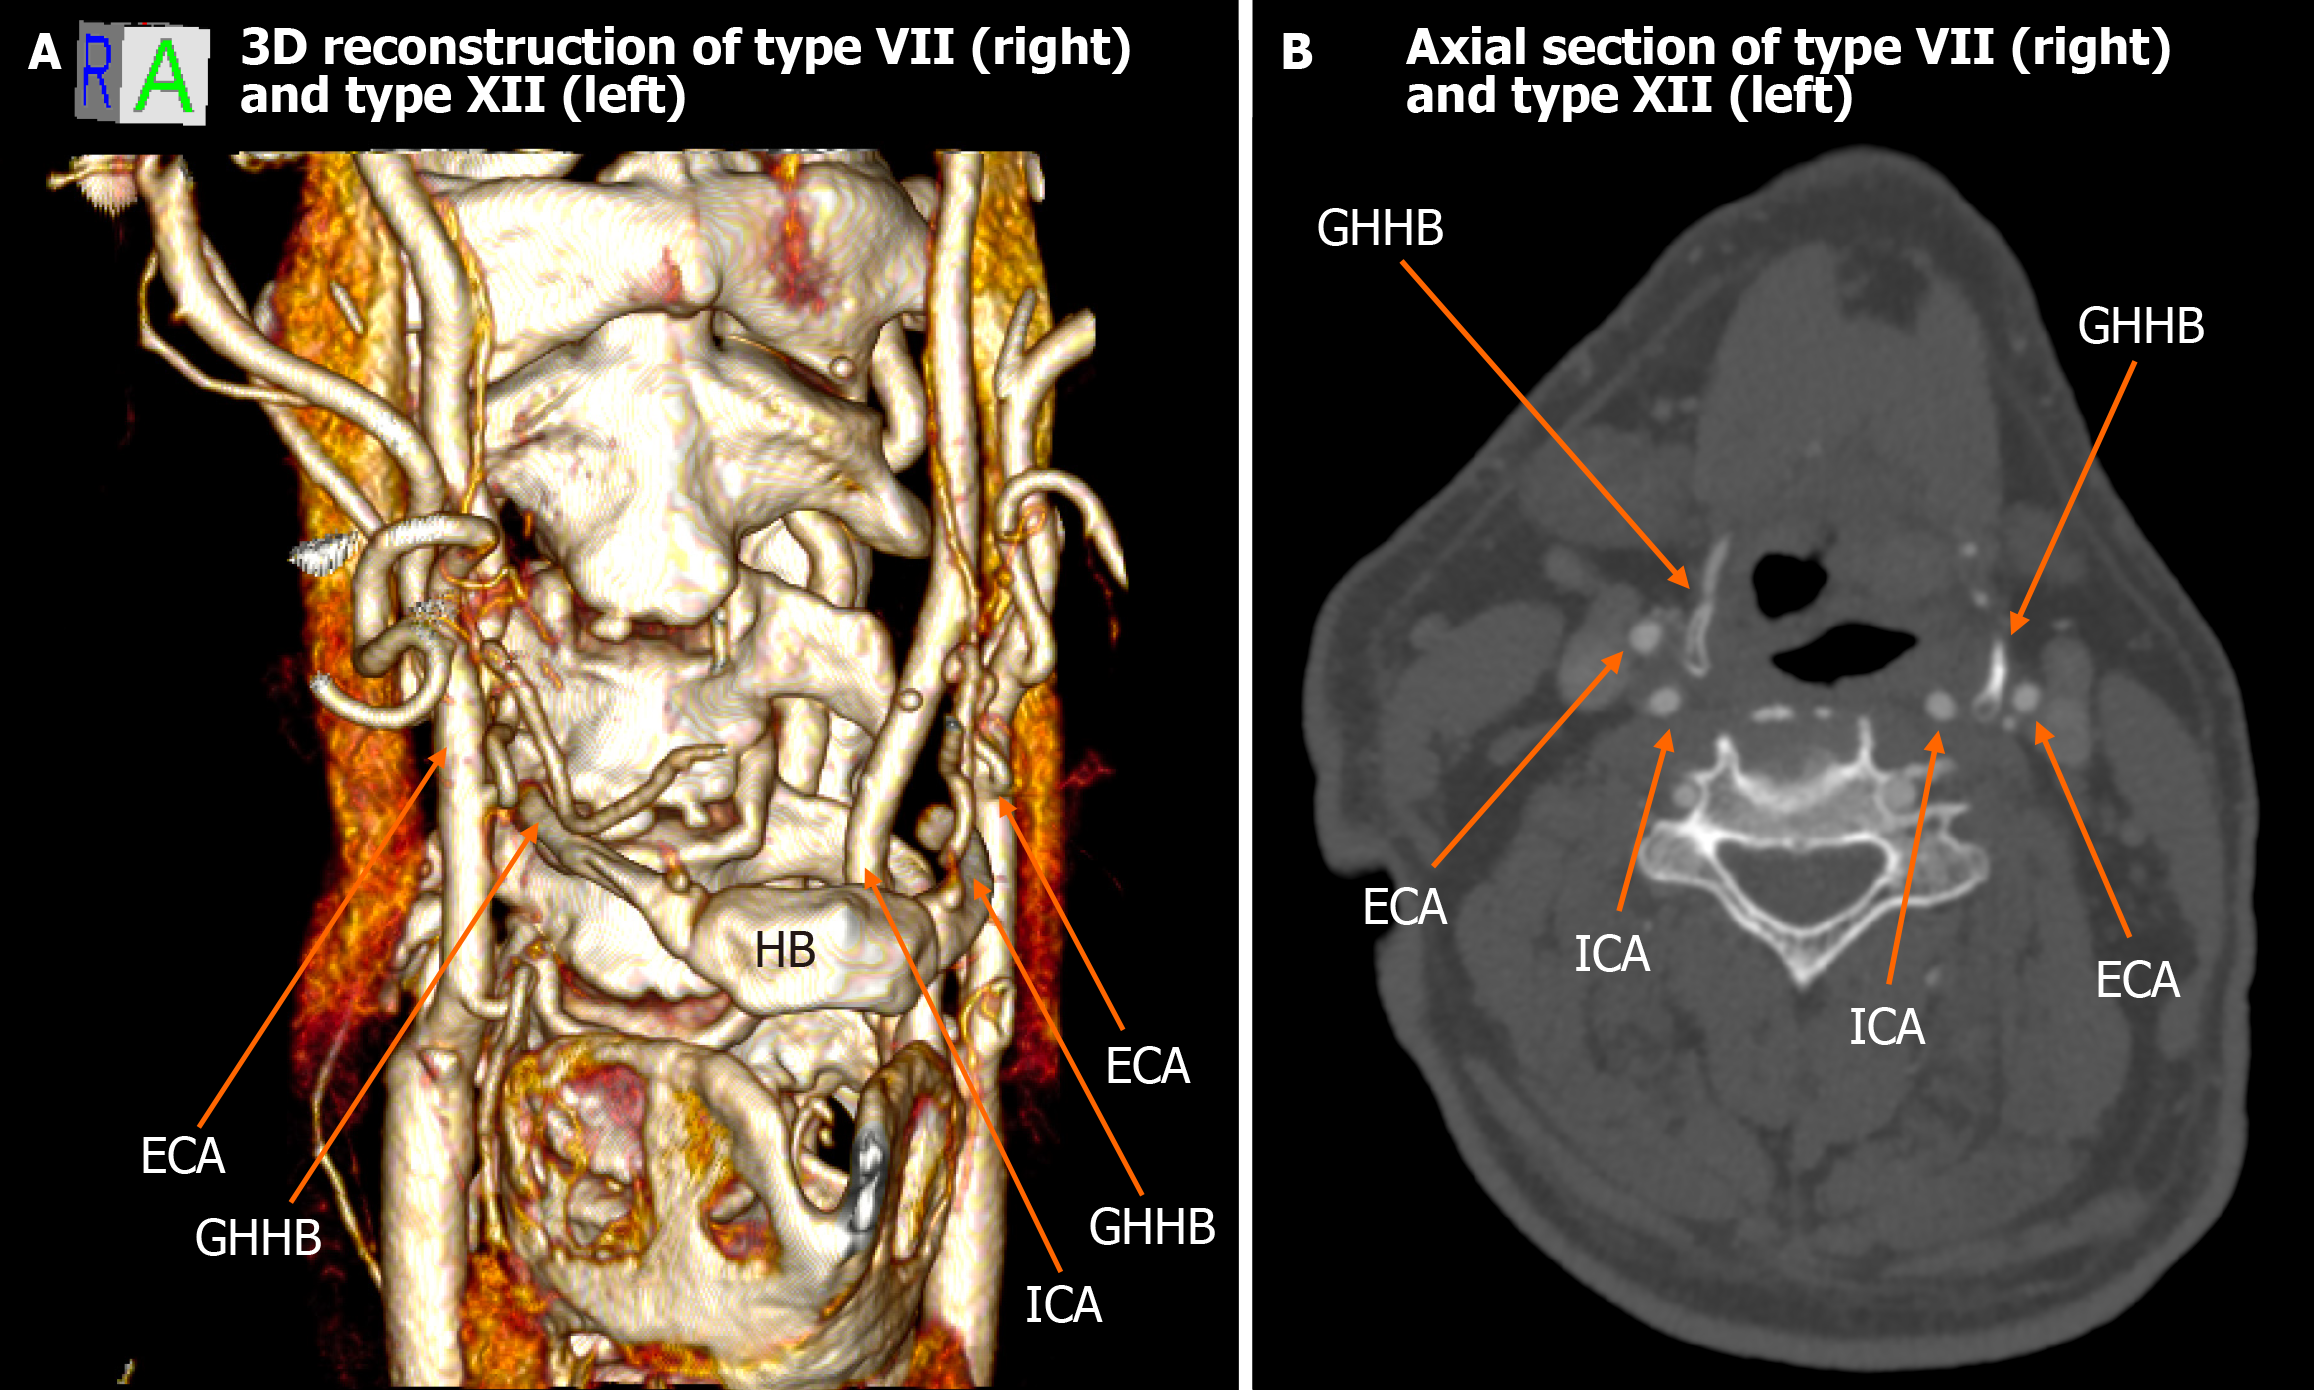

Figure 4 Type VII (right) and type XII (left).

A: The 3D rendering reveals that the right external carotid artery and internal carotid artery are both located lateral to the greater horn of hyoid bone (type VII), whereas on the left, the external carotid artery is medial, and the internal carotid artery is lateral to the greater horn of hyoid bone (type XII); B: Axial computed tomography confirms the described relationships. ICA: Internal carotid artery; ECA: External carotid artery; GHHB: Greater horn of hyoid bone; HB: Hyoid bone.